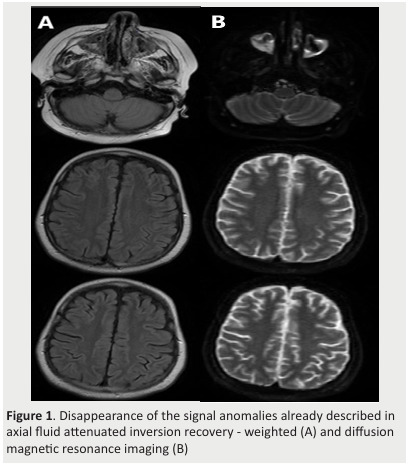

COVID-19 obscuring the diagnosis of ciclosporin-related posterior reversible encephalopathy syndrome.